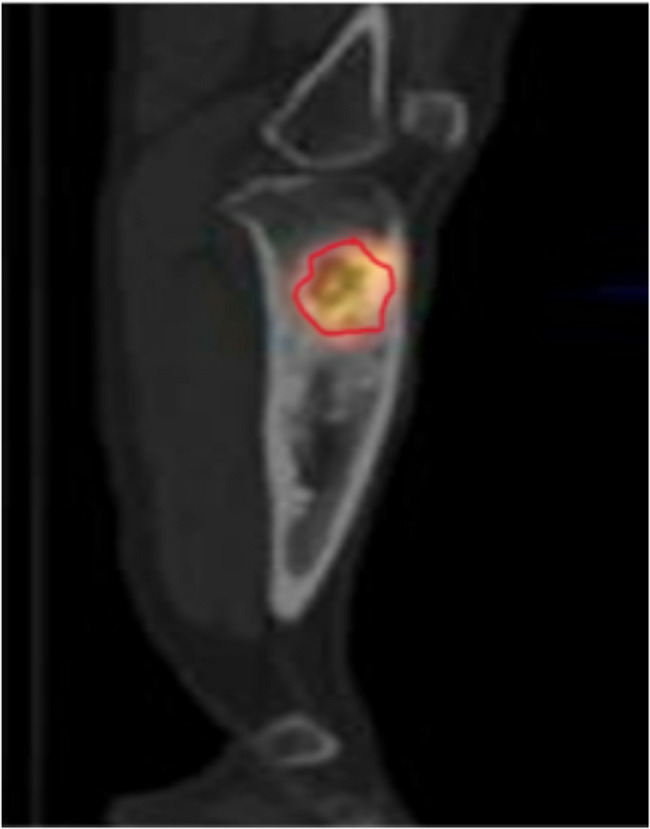

Results: Among the 70 patients, 20 cases were guided by X-ray, 30 cases by MRI, and 20 cases by SPECT. All patients underwent thorough debridement under the guidance of imaging modalities followed by external fixation. All cases were followed up and with a mean follow-up time of (12.2 ± 3.2) months. The recurrence rate of 35% in patients with X-ray as a guide was significantly higher than that of patients with MRI as a guide (10%) and SPECT as a guide (5%), and the difference between the three groups was statistically significant (P < 0.05).

Conclusion: For patients with osteomyelitis without metal internal fixation, the osteotomy surgical technique with MRI to guide the expansion of 0.5 cm distally and proximally, or with SPECT imaging to guide the surgical procedure in the area with 30-40% of the radioactive count contour (isocontour, ISO) had the advantages of low recurrence rate and good recovery of limb function, and the differences were not statistically significant. For patients with osteomyelitis with metal internal fixation, the osteotomy surgical technique with SPECT to guide the surgical procedure had the advantages of low recurrence rate and good recovery of limb function. In patients with osteomyelitis with metal internal fixation, SPECT was used as a guide to determine the extent of the osteomyelitis lesion, and osteotomy in the area with 30-40% of ISO was more effective than MRI.